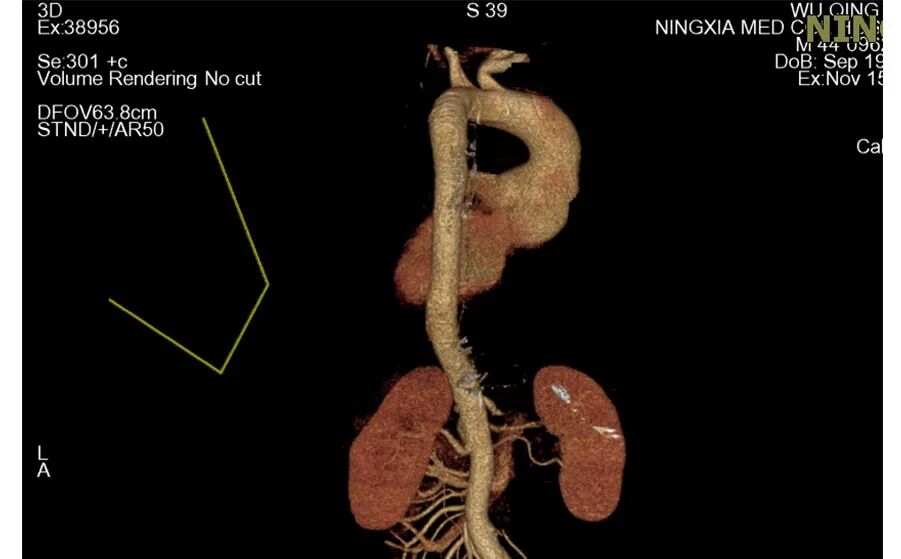

Bentall术前主动脉CTA 例1

为什么叫哈巴狗钳2023学术荟萃|王云:右侧肋间小切口体外循环心脏手术_https://www.jmylbn.com_新闻资讯_第9张

为什么叫哈巴狗钳2023学术荟萃|王云:右侧肋间小切口体外循环心脏手术_https://www.jmylbn.com_新闻资讯_第10张